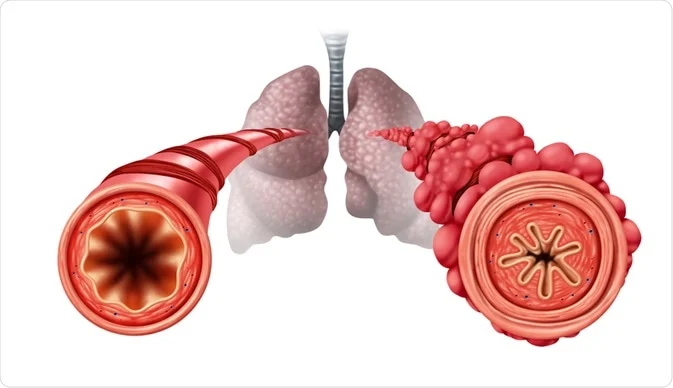

બ્રોકાઇ અને બ્રોન્કીલ્સ ટ્યુબના ઇન્ફલામેશન ને બ્રોન્કાઇટીસ તરીકે ઓળખવામાં આવે છે. બ્રોન્કાઇટીસને ‘બ્લુ બ્લોટર’ તરીકે પણ ઓળખવામાં આવે છે.

બ્રોન્કાઇટીસ એટલે લોવર રેસ્પિરેટ્રી ટ્રેક ના બ્રોન્કાઇ મા ઇન્ફેક્શન તથા તેના ઇન્ફ્લામેશન ને બ્રોન્કાઇટીસ કહેવામાં આવે છે. બ્રોન્કાઇટીસ માં ઇન્ફેક્શન ના કારણે બ્રોન્કાઇમાં મ્યુક્સ નું પ્રોડક્શન થાય છે તેના કારણે બ્રિધિંગ ડિફિકલ્ટિસ ની કન્ડિશન અરાઇઝ થાય છે.

બ્રોન્કાઇક્ટેસિસ એ ક્રોનિક રેસ્પાયરેટરી કન્ડિશન છે જેમાં બ્રોન્કાઇ અને બ્રોન્કીયોલ્સનું એબનોર્મલ અને ઇરરિવર્સિબલ ડાયલેશન, ઇન્ફલામેશન અને થીકનિંગ જોવા મળે છે.

જેના પરિણામે તેમાં મ્યુકસ નું એક્યુમ્યુલેશન થાય છે અને એરવેમાંથી મ્યુકસ એ પ્રોપર્લી ક્લિયર થતો નથી જેના કારણે રીકરંટ રેસ્પાયરેટરી ઇન્ફેક્શન જોવા મળે છે.